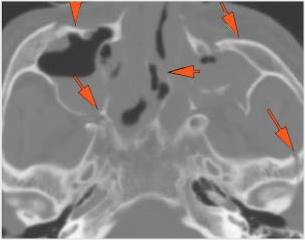

Zygomatico-orbital region and globes

Central Skull Base and Calvarium